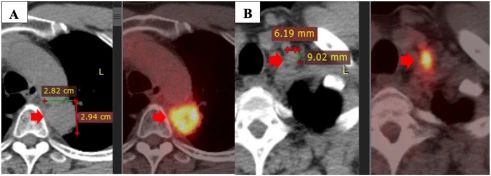

盡管如此,該疾病在 2020 年 5 月繼續(xù)發(fā)展。PET/CT 掃描顯示原發(fā)性腫瘤大小為 28×29 mm,最大標準化攝取值(SUVmax)為 11.2,粘附在縱隔胸膜和主動脈上。此外,左側(cè)鎖骨上淋巴結(jié)的大小為 9×6 mm,左側(cè)門靜脈的一些小淋巴結(jié)大小小于 10 mm。

注:一線治療一年后疾病進展:原發(fā)性腫瘤(A),左鎖骨上淋巴結(jié)(B)。